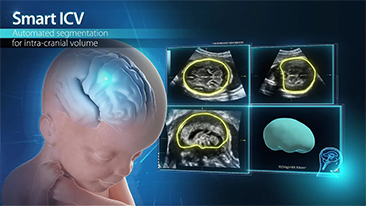

Geoptimaliseerde workflows in gynaecologie en verloskunde zijn noodzakelijk ter ondersteuning van grote pati?ntenvolumes aan screeningbezoeken voor vrouwen. Misvormingen van het centrale zenuwstelsel (CZS) zijn bijvoorbeeld een van de meest voorkomende aangeboren afwijkingen. Als gevolg van verschillende beeldvormingscondities, zoals een slechte foetale positie, is de MSP zeer moeilijk te vinden in een 2D-echografie. Daarom kunnen geautomatiseerde detectie en metingen de scaneffici?ntie sterk verbeteren.